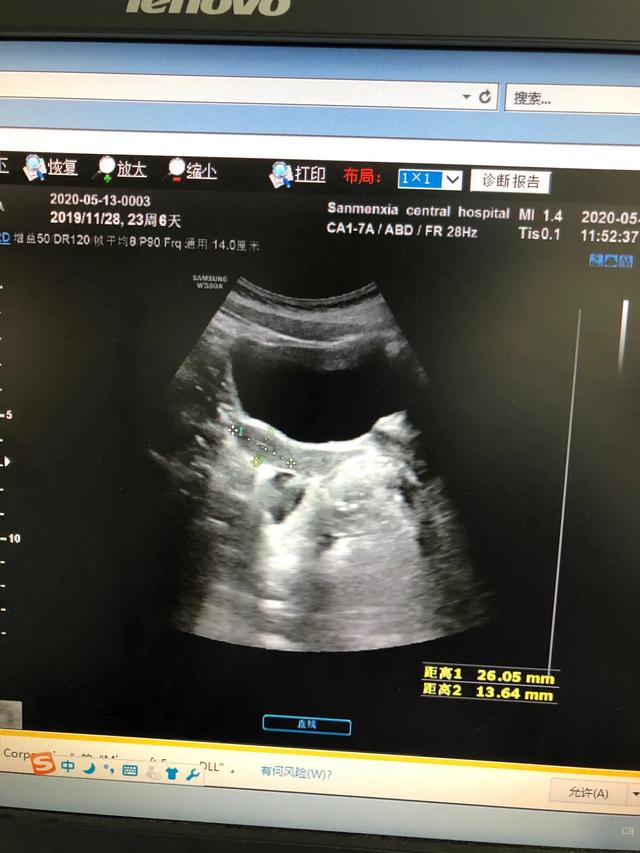

下图是一例患儿性早熟的B超结果、胸片结果及血清学化验结果。

从检查结果来看,B超显示子宫卵巢有囊性回声;胸片显示乳腺发育;而血清学指标,促黄体生成素的峰值是13.09,促卵泡的峰值是20.91,LH/FSH=62.60%。